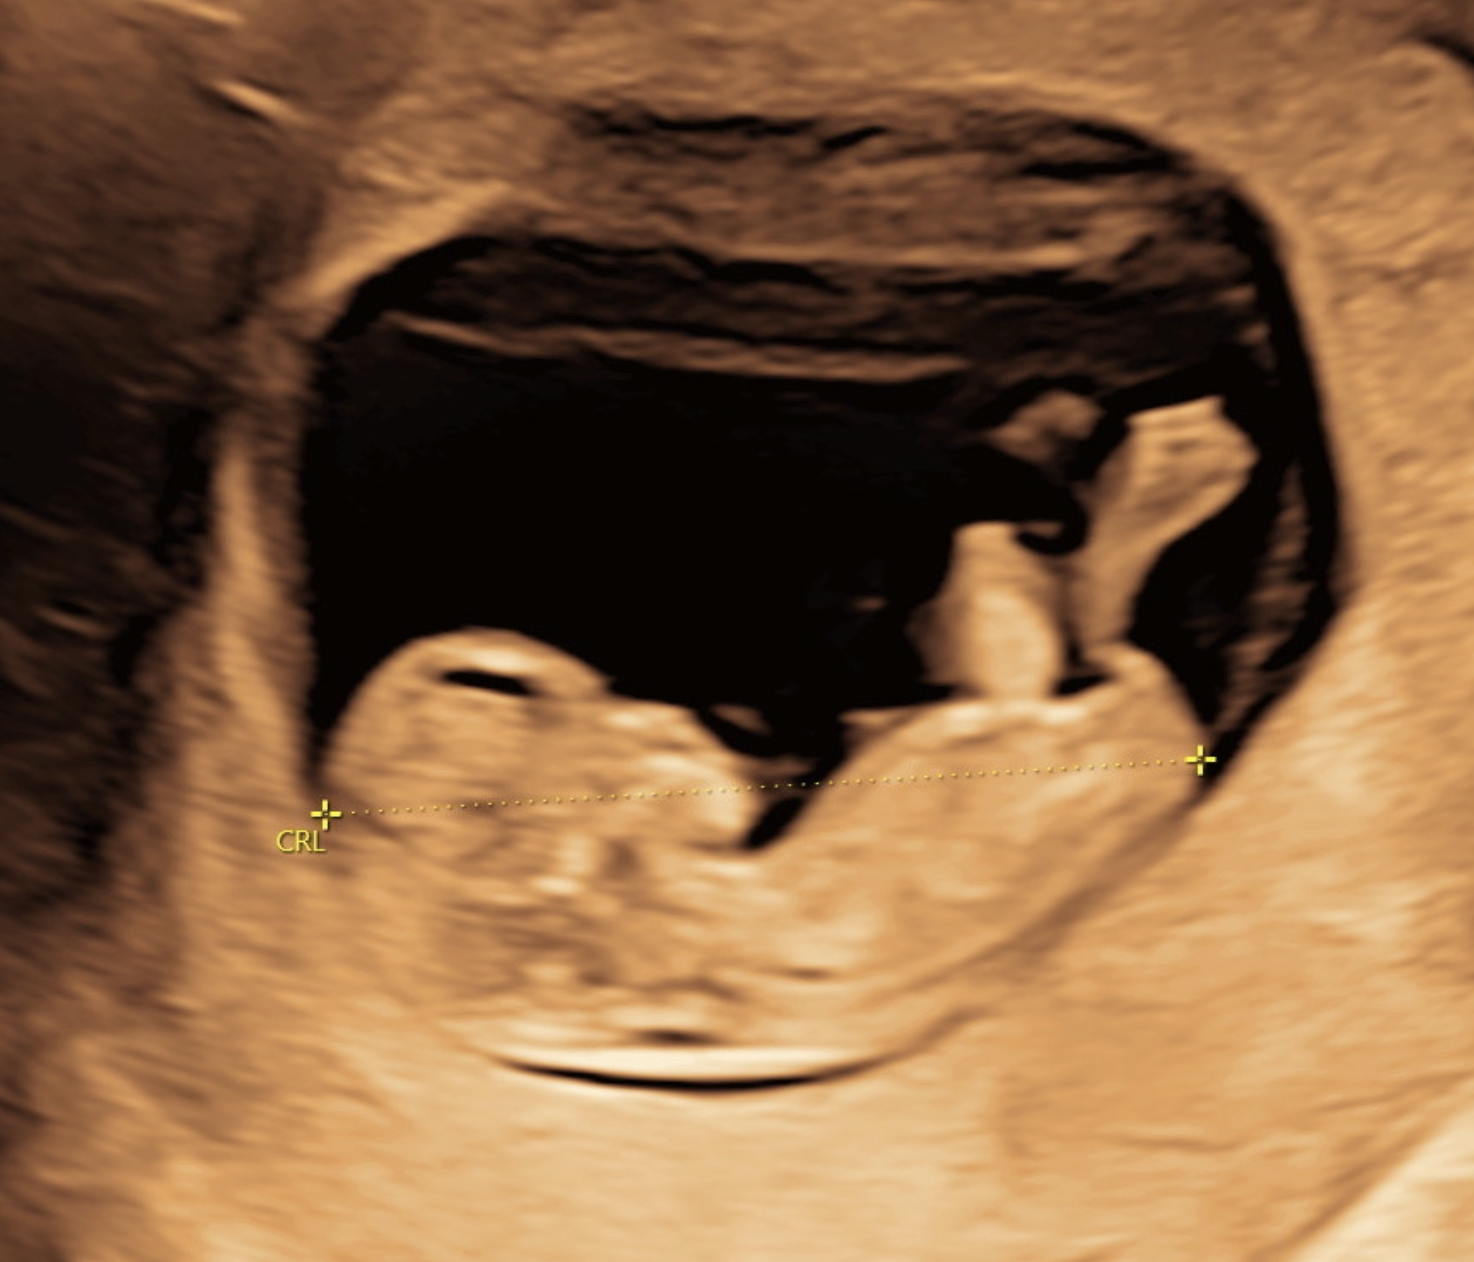

Tidlig scanning som også er kaldet for tidlig graviditetsscanning, kan vi udføres fra uge 5+0, og er en af de første undersøgelser, som gravide vælger for at bekræfte graviditeten og få en præcis vurdering af fostrets udvikling. Med tidlig scanning hos A-scan, bekræfter vi hjerteblink, fastlægger antallet af fostre og beregner en præcis terminsdato. Denne graviditetsscanning er afgørende for at sikre, at din graviditet forløber som forventet, og at alt udvikler sig normalt.

Hos os kan du få tidlig scanning allerede fra uge 5+0. For det mest præcise resultat anbefaler vi scanning fra uge 6+3. Start din graviditet med vished – ro og tryghed.